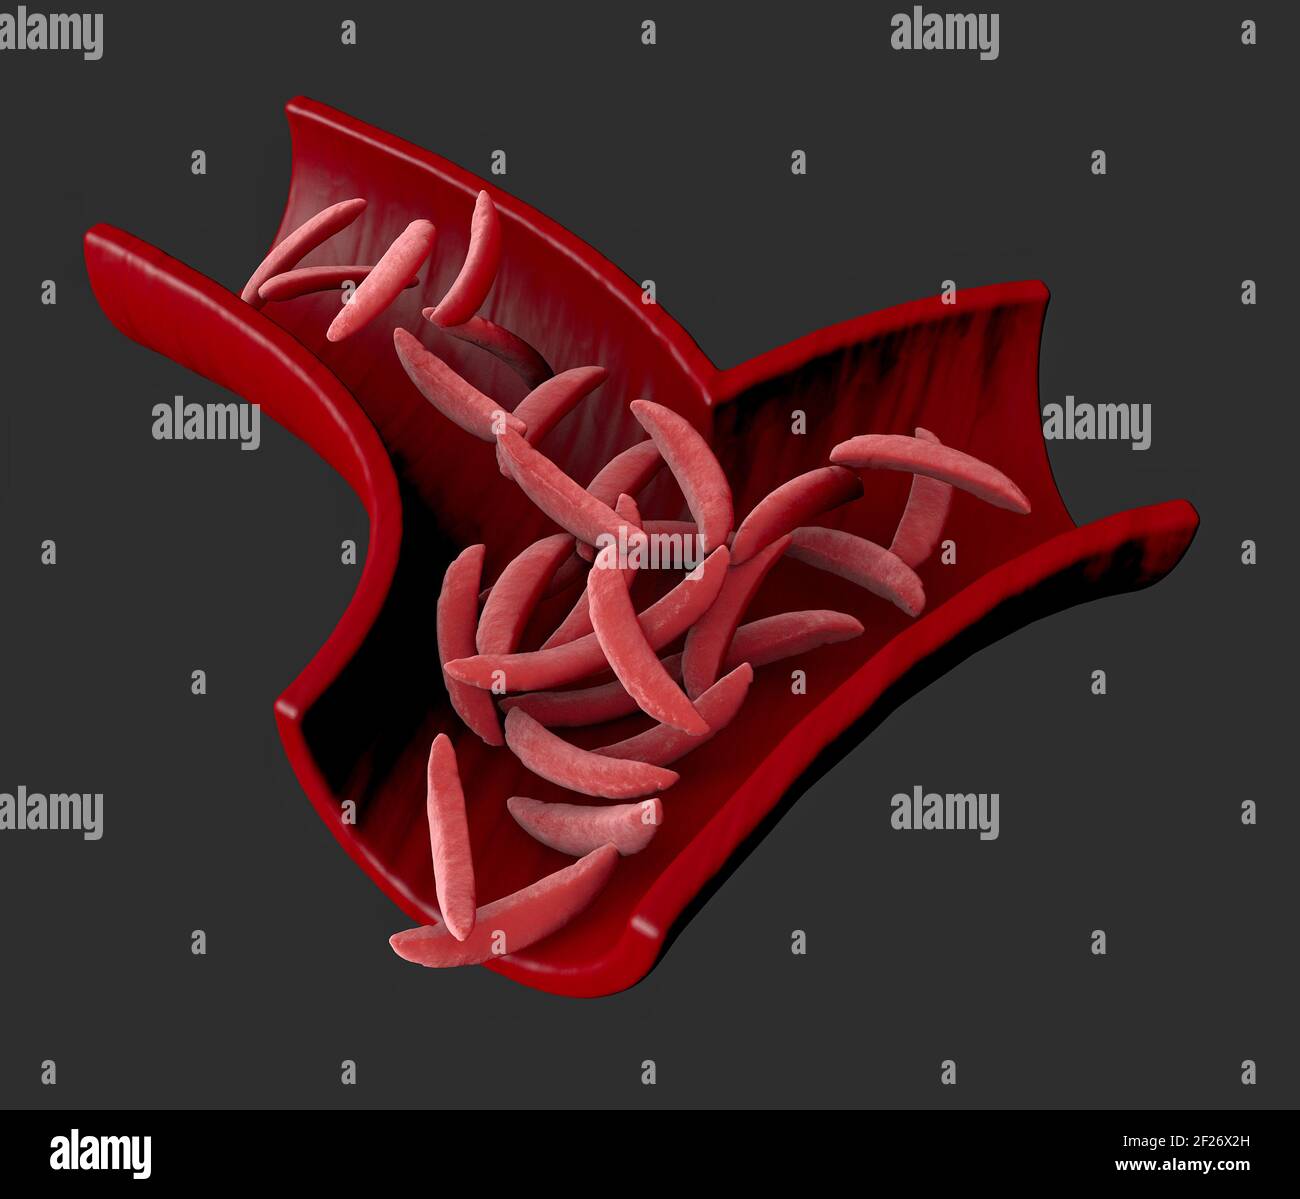

Sickle cell disease is a group of blood disorders. Sickle cell anaemia. It results in an abnormality in the oxygen-carrying protein haemoglobin Stock Photohttps://www.alamy.com/image-license-details/?v=1https://www.alamy.com/sickle-cell-disease-is-a-group-of-blood-disorders-sickle-cell-anaemia-it-results-in-an-abnormality-in-the-oxygen-carrying-protein-haemoglobin-image414430313.html

Sickle cell disease is a group of blood disorders. Sickle cell anaemia. It results in an abnormality in the oxygen-carrying protein haemoglobin Stock Photohttps://www.alamy.com/image-license-details/?v=1https://www.alamy.com/sickle-cell-disease-is-a-group-of-blood-disorders-sickle-cell-anaemia-it-results-in-an-abnormality-in-the-oxygen-carrying-protein-haemoglobin-image414430313.htmlRF2F26X2H–Sickle cell disease is a group of blood disorders. Sickle cell anaemia. It results in an abnormality in the oxygen-carrying protein haemoglobin